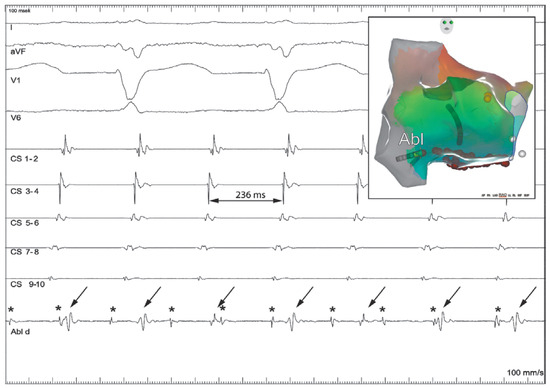

Case report